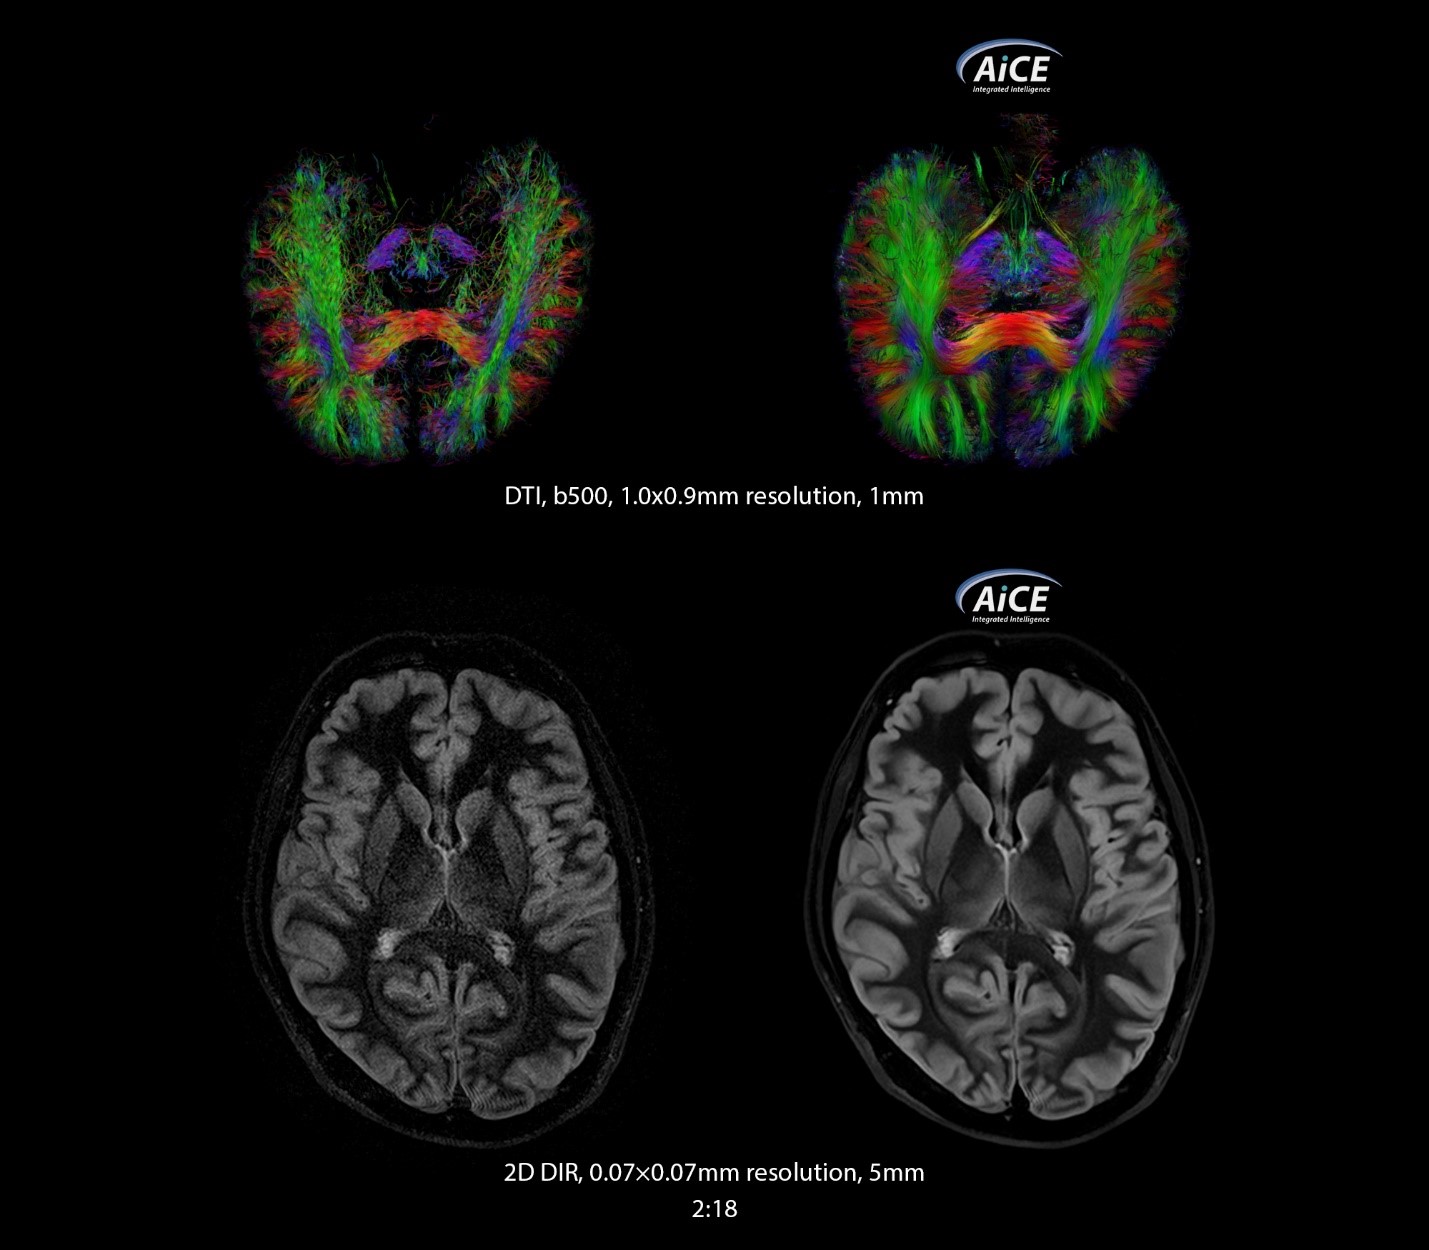

Це досягається завдяки застосуванню методу Compressed SPEEDER до послідовностей FSE, застосуванню алгоритмів штучного інтелекту AiCE, технології одночасного збудження кількох зрізів Multiband.

AiCE - чіткі зображення без шуму.

Використовуючи величезну обчислювальну потужність глибокої конволюційної нейронної ме-режі (DCNN), AiCE навчається відновленню даних на МРТ, щоб реконструювати зображення без шуму, це призводить до значного покращення якості зображення.

• Інтелектуально видаляє шум;

• Покращує значення SNR;

• Підвищує розподільчу здатність;

• Розширює анатомічну деталізацію.